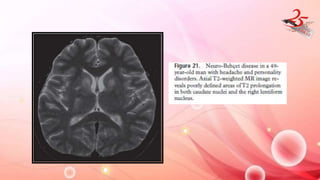

NEURO – BEHCET DISEASE

• Behcet syndrome : uveitis , oral ulcers and genital ulcers.

• CNS involvementin 4-49%

• CLINICAL FEATURES : Headache , dysarthria , cerebellar signs ,

sensory signs and personality change.

IMAGING FINDINGS:

• T2 hyperintense and T1 hypointense and CE with vasogenic edema

at brainstem, basal ganglia (bilateral involvement in one-third of

cases), and thalamus , WM(LC)

NEURO – BEHCETDISEASE • Behcet syndrome : uveitis , oral ulcers and genital ulcers. • CNS involvementin 4-49% • CLINICAL FEATURES : Headache , dysarthria , cerebellar signs , sensory signs and personality change. IMAGING FINDINGS: • T2 hyperintense and T1 hypointense and CE with vasogenic edema at brainstem, basal ganglia (bilateral involvement in one-third of cases), and thalamus , WM(LC)